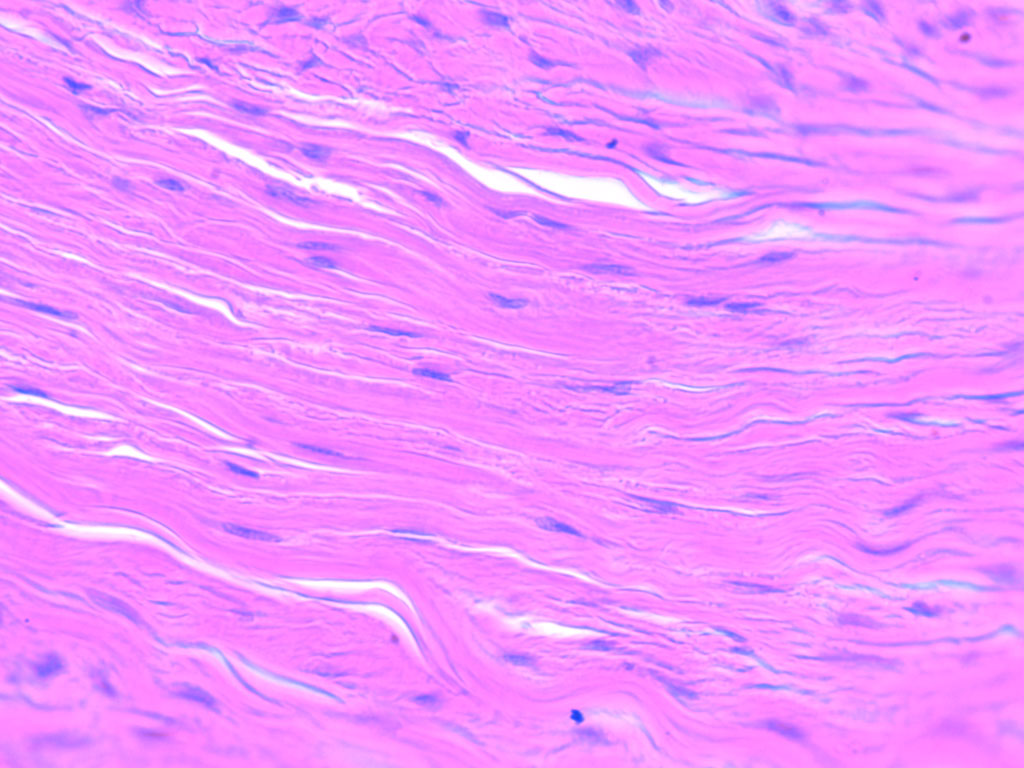

collagen fibers

straight, strong

Dense connective tissue (tendons and ligaments)